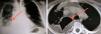

Se trata de un varón de 63 años que ingresa a nuestro cargo por dolor en el hombro derecho, de una semana de duración, y tres días de fiebre alta. Presentaba una tumoración dolorosa en la región esternoclavicular derecha y discreta hipoventilación en la base pulmonar del mismo lado. El resto de la exploración fue anodina y la anamnesis no reveló factores de riesgo. Tenía leucocitosis con neutrofilia, velocidad de sedimentación glomerular (VSG) y fibrinógeno elevados, sin otras alteraciones analíticas. La radiografía de tórax mostró una imagen condensante en lóbulo superior derecho y condensación difusa de la base derecha (fig. 1). La radiografía de hombro no mostró alteraciones. En la TC torácica se apreció desestructuración de los bordes articulares y una colección líquida periarticular que se continuaba subclavicular, pleural anterior y en base pulmonar derecha (fig. 1).